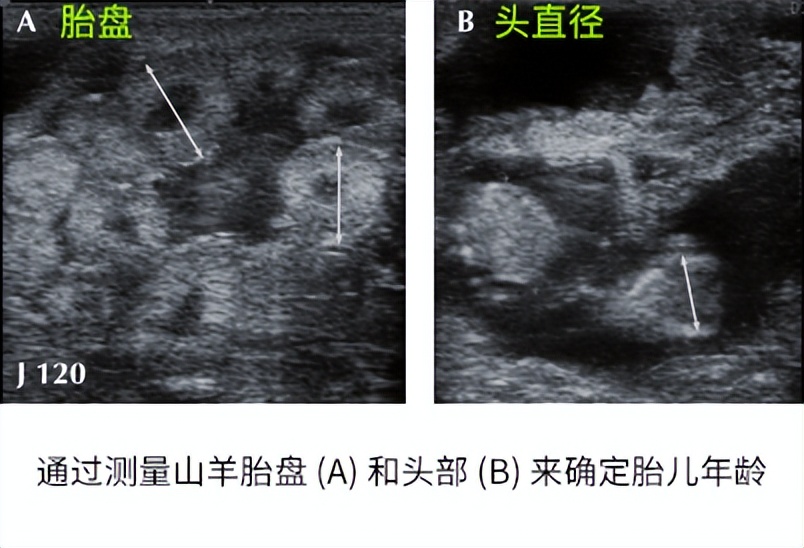

使用羊用B超机确定妊娠母羊胎龄可以为饲养管理、预期产犊提供便利。母羊妊娠胎龄的确定基于胚胎和胎儿尺寸的测量,如胚胎囊泡直径、胚胎长度、长骨长度(胫骨、股骨、肱骨、尺骨或桡骨)、双层直径、胸径、胎儿心率,胎盘直径和眼腔直径(看下图)。

双顶径与胎儿年龄密切相关(R 2 ≥ 0.95)。 从妊娠第 36 天到妊娠结束,该参数很容易识别和测量,但其相关性在第 3 个月后下降。